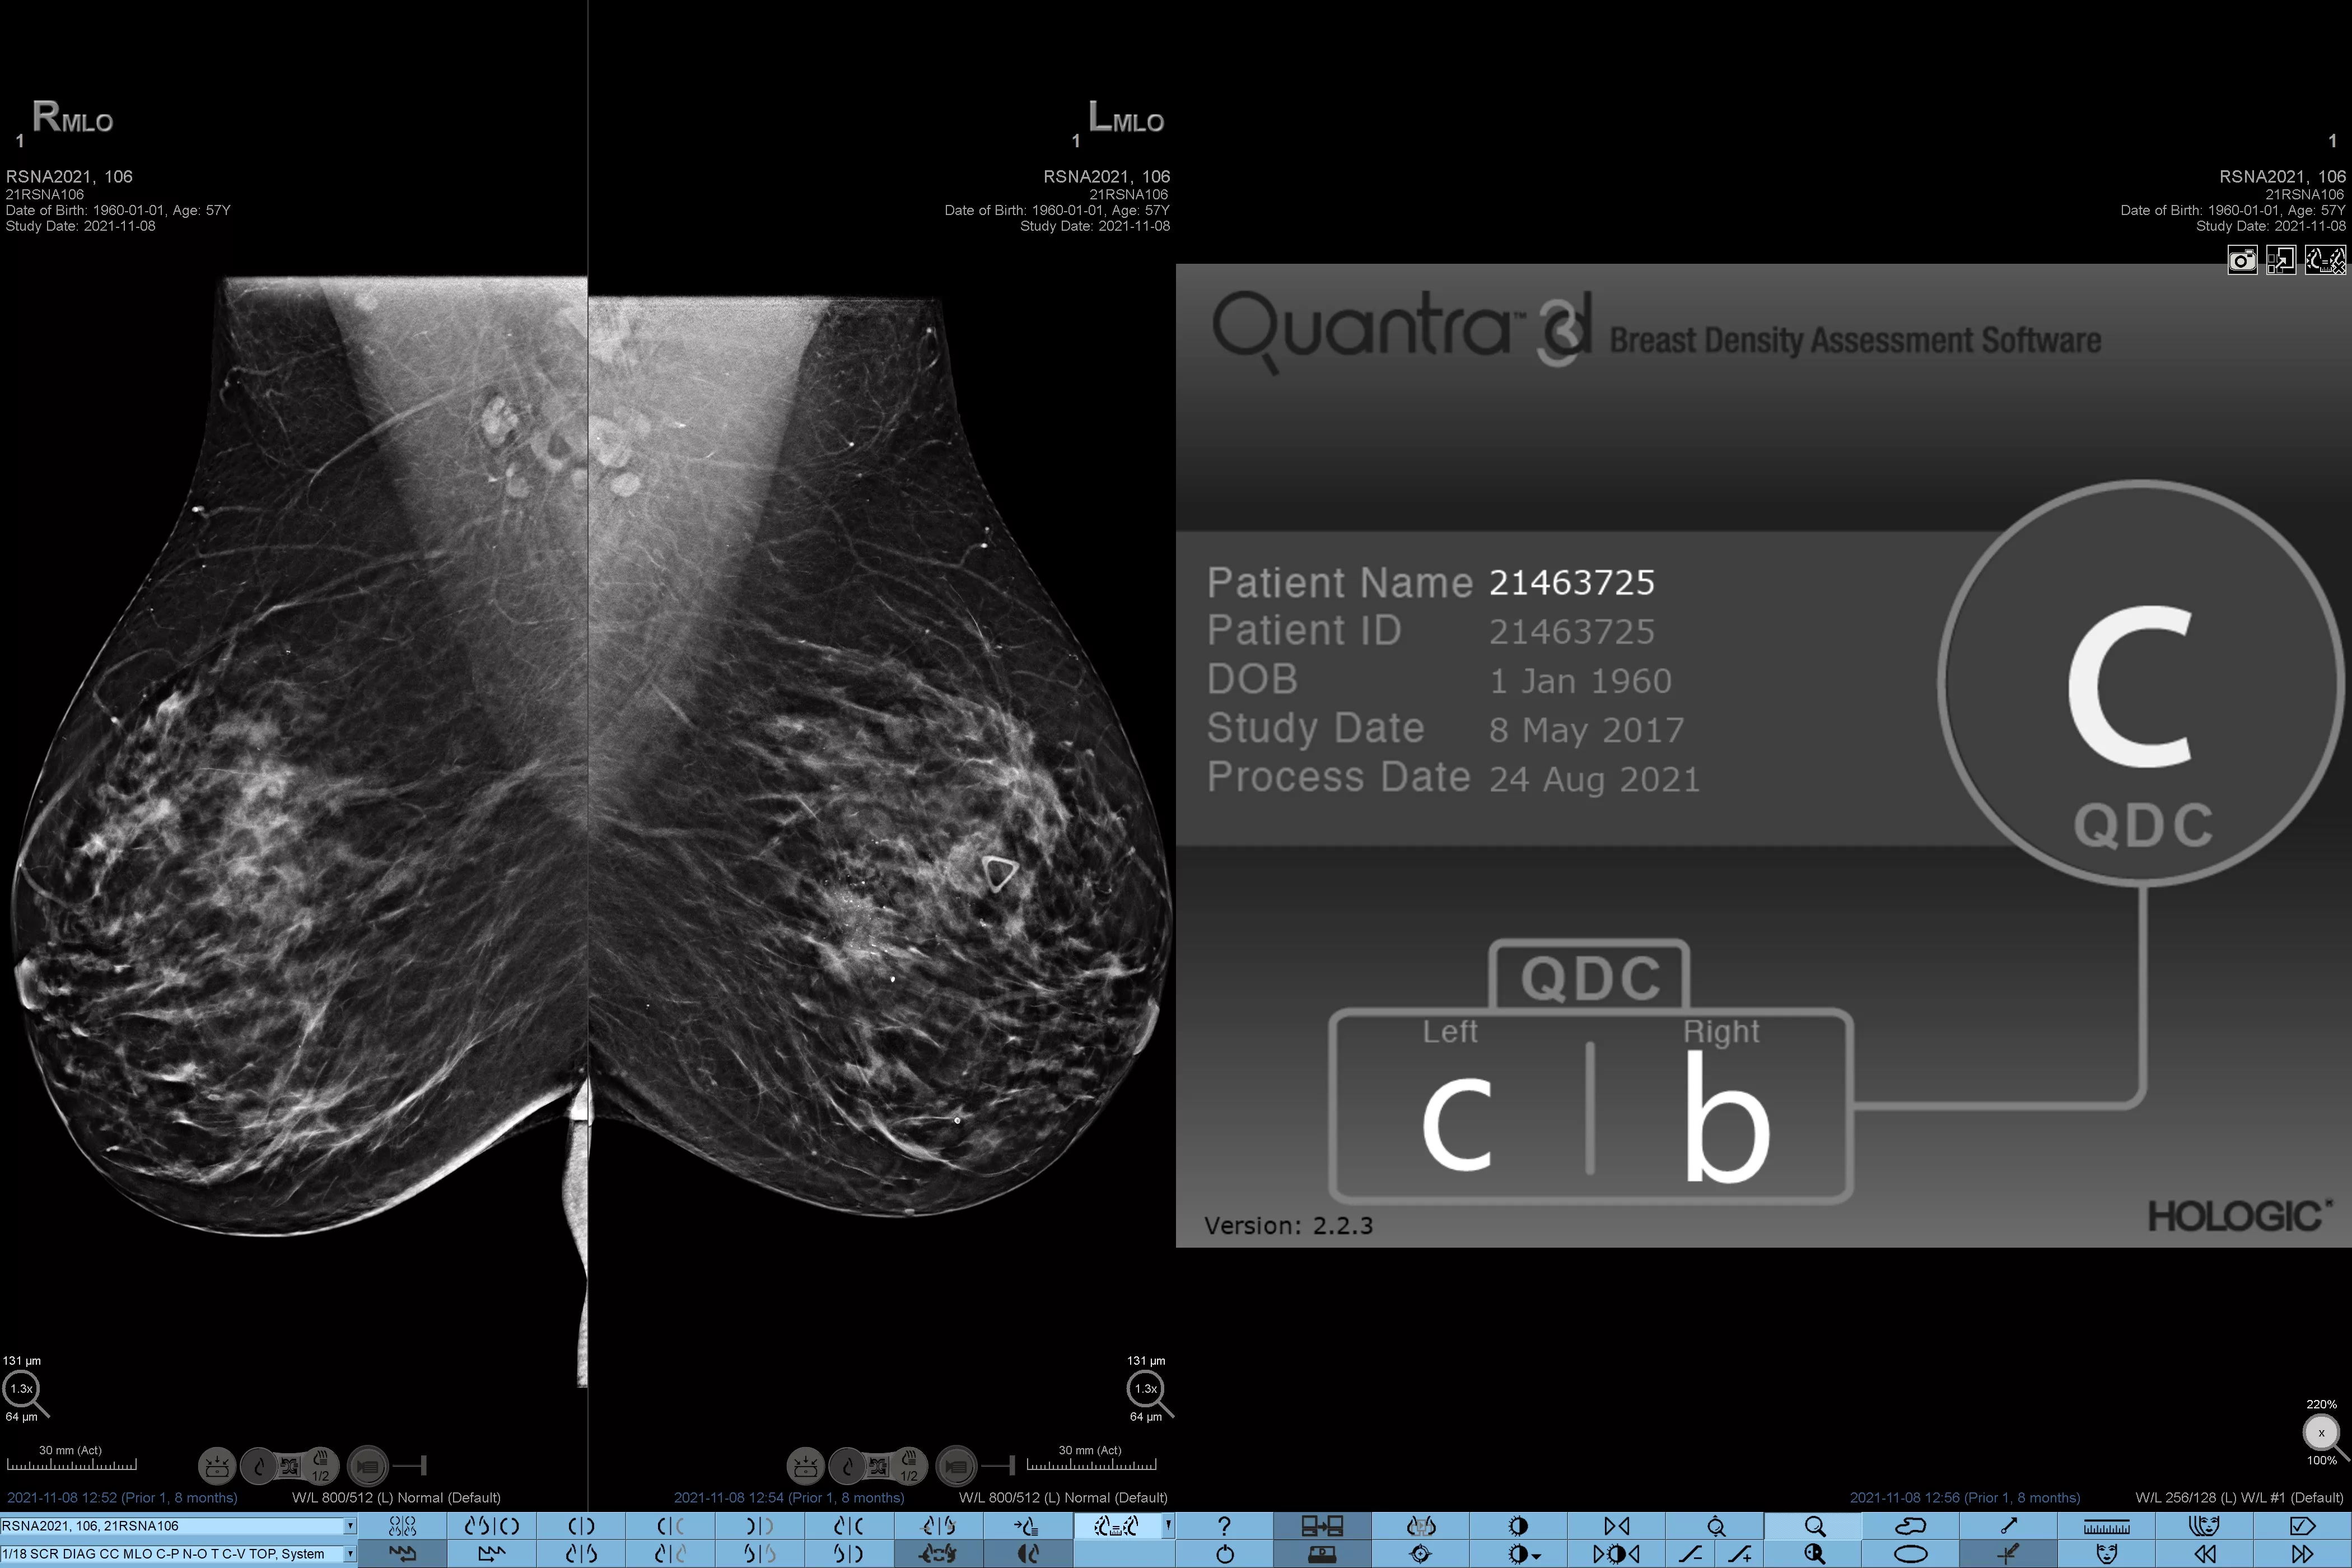

Het is bekend dat een hogere borstdichtheid het risico van een vrouw op borstkanker vergroot.1 De behoefte aan nauwkeurige, objectieve analyses is daarom cruciaal. Aangedreven door machine learning analyseert Quantra-technologiesoftware zowel 2D™- als tomosynthesebeelden op verdeling en textuur van parenchymweefsel. Het deelt borsten in vier categorieën voor borstsamenstelling in, in overeenstemming met de richtlijnen van de American College of Radiology (ACR) BI-RADS Atlas 5e editie.2

Objectief machine-learningalgoritme dat de borstdichtheidscategorie toewijst op basis van analyse van de textuur en patronen van het borstweefsel.